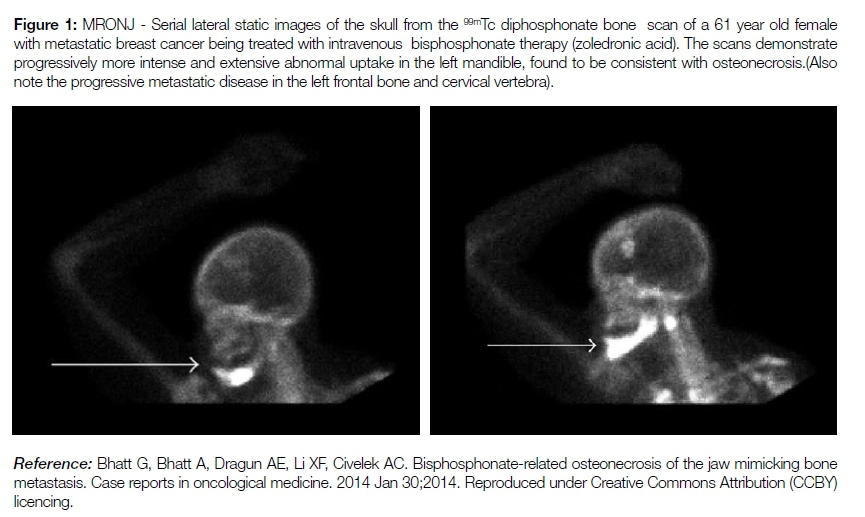

Bisphosphonates bind to osteoclasts in areas of active bone resorption to reduce osteoclastic recruitment; longevity and activity. During the early stages of MRONJ, areas of reduced uptake are consistent with the decreased vascularity of diseased bone.

As the disease progresses, bone scintigraphy can show areas of radionuclide uptake reflective of osteoblastic hyperactivity in a subchondral location.9 Scintigraphy is thus proposed as a screening tool by some authors to detect subclinical osteonecrosis in patients receiving bisphosphonates (see figure 1).9,10 Condylar hyperplasia (CH) is a rare bone disorder that is characterised by excessive growth of the condylar process of the mandible. It is typically a unilateral disorder (UCH), with resultant facial asymmetry, deformity, and malocclusion. It usually presents predominantly in female patients during adolescence. UCH is classified as a self-limiting condition and is characterised by a stationary and active phase. UCH is best managed during the stationary phase to prevent further deformity and unnecessary disruption of the TMJ. Functional imaging is uniquely able to differentiate between the two phases based on a qualitative and quantitative assessment of the uptake on the affected side, which will be asymmetrically higher during the active phase with a return to normal during the stationary phase.